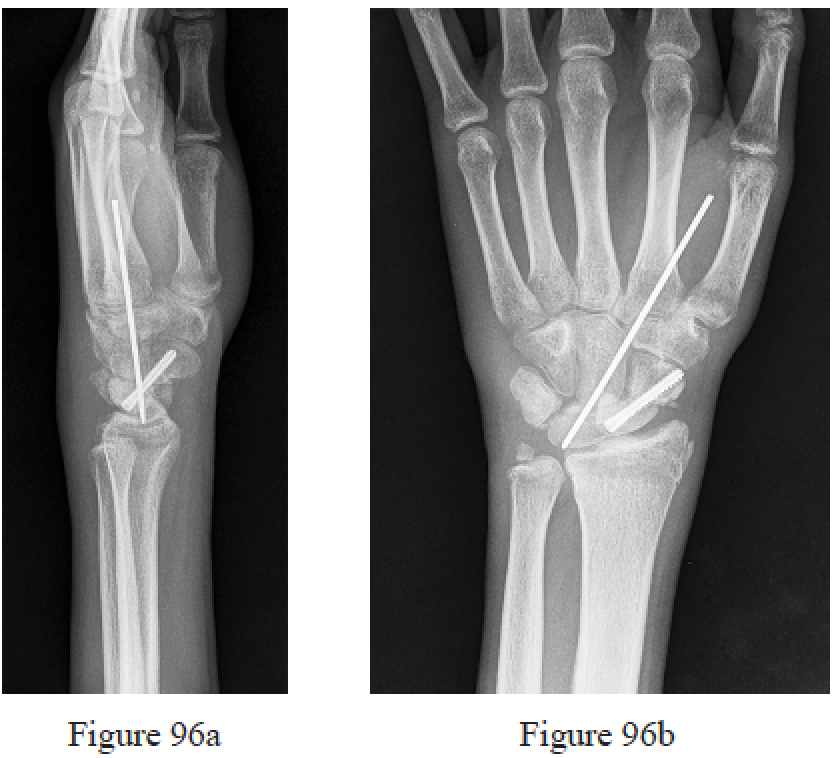

Figure 140 is the T1-weighted MR image of a 24-year-old man who has a 6-month history of right wrist pain. He fell on an outstretched hand while skateboarding 18 months ago and had pain that resolved after several weeks. Radiographs of his right wrist demonstrate an established scaphoid nonunion at the waist with a humpback deformity and no signs of arthritis. What is the best next step?